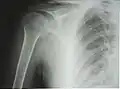

К моменту рождения только проксимальный эпифиз состоит из хрящевой ткани, из-за чего головка плечевой кости практически не определяется на рентгенограмме. В ходе взросления последовательно возникает три точки окостенения проксимального эпифиза:

К 4—6 годам указанные центры сливаются в единую головку плечевой кости. Замещение метаэпифизарного хряща на границе проксимального эпифиза и диафиза костной тканью (синостоз) наступает в подростковом возрасте, благодаря чему продолжается рост кости в длину. На рентгенограмме ребёнка или подростка определяется характерный светлый участок на месте метаэпифизарного хряща, который может быть принят за перелом или трещину[4].

Рентгенограмма верхней части плечевой кости с выраженной хирургической шейкой